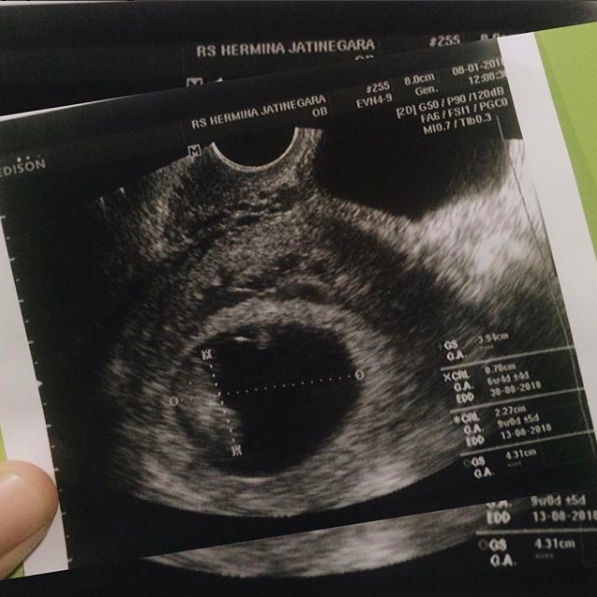

DESEMBER 2017: HAMIL

Salah satu pertanyaan yang saya ajukan di setiap wawancara kerja adalah: “Boleh hamil?” Pertanyaan simpel yang jawabannya beragam: ada HRD yang jawab “Selo bae, boleh lah”, ada juga yang jawab ketus sampe bikin sakit hati melebihi sakit hati saat picingan di tolak + digantungin fixer sampe liputan zonk, dan sampe jawaban paling sae: “Boleh asal ada suaminya.” (YA MENURUT LO AJA? :’) )

Dan Alhamdulilah perusahaan tempat saya kerja sekarang tidak memilik masalah dengan “pekerja perempuan yang hamil” (I really want to talk about this so bad, but not today).

Alhamdulillah di awal bulan Desember setelah ngakak karena baca strip testpack dua garis, saya positif hamil. Dari dulu nggak pernah nunda punya anak sih, tapi saya dan suami kan LDR, jadi ya mikir positifnya aja (ena-ena nya jarang, wkwkw).

Kadang geli juga gitu sama keluarga/teman/kenalan yang langsung nyosor nge-judge pasangan LDR gini-gitu jadi nanti anaknya gini-gitu, ya Allah gemaznya, pengen sa pencetin komedonya sampe berdarah (ngeriks).

So here I am, 4 months pregnant and still amaze by how 2017 brings me to this step. Entah apalagi kejutan yang akan ada di 2018 nanti, we’ll see. Rencana Allah itu selalu tidak terduga ☺